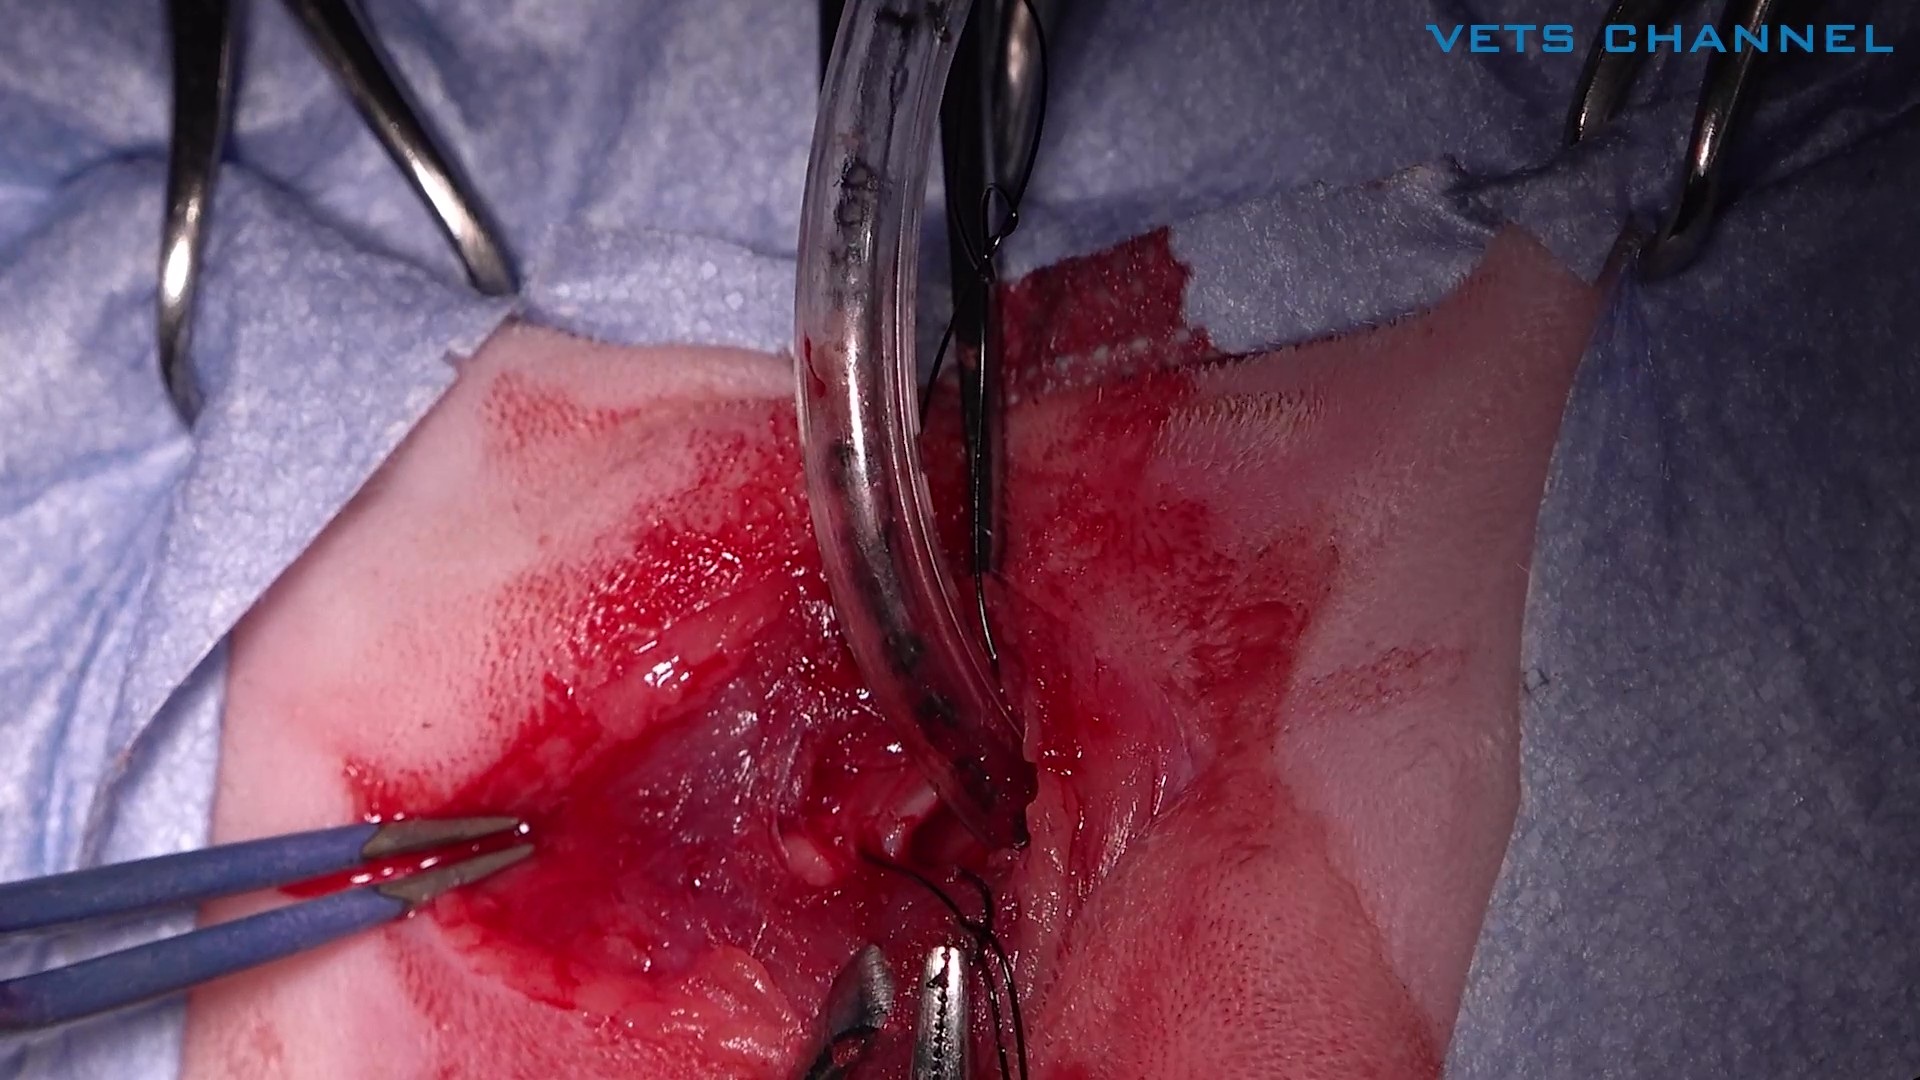

一次気管切開+気管内腫瘤切除術

- OPE

- 軟部外科

- 呼吸器科

- 腫瘍科

- 猫

小林 正行先生 (動物先端医療センター・AdAM)

20分

2025/10/17

一次気管切開+気管内腫瘤切除術

- OPE

- 軟部外科

- 呼吸器科

- 腫瘍科

- 猫

小林 正行先生 (動物先端医療センター・AdAM)

20分

2025/10/17